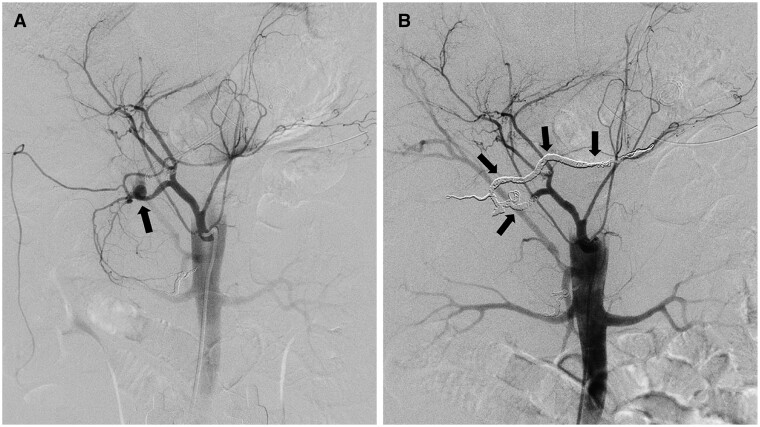

A 63-year-old man underwent transcatheter arterial embolization (TAE) using a mixture of N-butyl-2-cyanoacrylate (NBCA) and iodized oil to treat acute gastrointestinal (GI) bleeding. The procedure was initially successful; however, the patient developed ileus >1 month later and subsequently underwent several surgeries to treat the multiple metachronous ileal stenoses. The flux of a small amount of off-target glue was the primary cause of these complications. As the patient had few symptoms in the first month post-TAE, however, affirming the diagnosis took time. A detailed review of plain CT scans was a decisive factor in achieving the final diagnosis. This case demonstrates that TAE using an NBCA-iodized oil mixture effectively treats acute GI bleeding. However, a complication such as off-target embolization is likelier to occur because of a combination of certain factors such as vascular anatomy, complexity of the procedure, and NBCA dilution. Close observation using plain CT should be performed for the identification of off-target embolization occurrence even in cases of successful TAE.